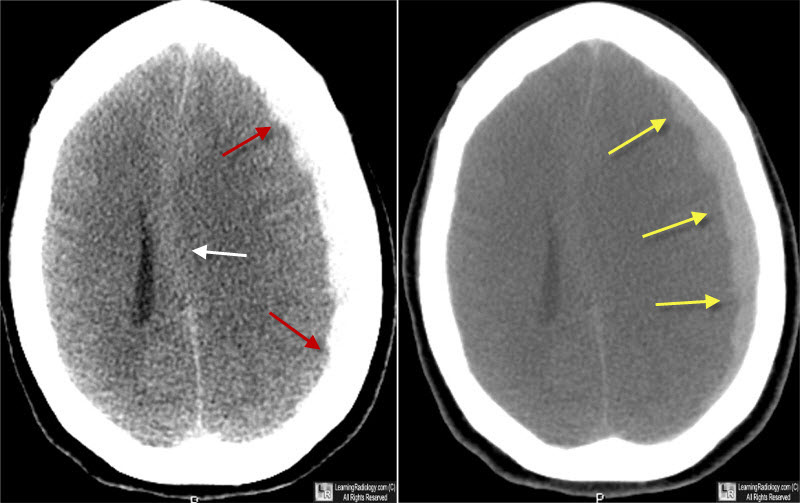

Craniectomía descompresiva versus craneotomía para el hematoma subdural agudo traumático

14 agosto 2023

Encontramos una variación sustancial entre centros en el empleo de la craniectomía descompresiva (CD) versus craneotomía para el hematoma subdural agudo traumático. Esta variación en la estrategia de tratamiento no resultó en un resultado funcional diferente. Estos hallazgos sugieren que la CD primaria debe restringirse a pacientes recuperables en los que no es posible el reemplazo inmediato del colgajo óseo debido a la inflamación cerebral intraoperatoria. eClinicalMedicine, 9 de agosto de 2023.